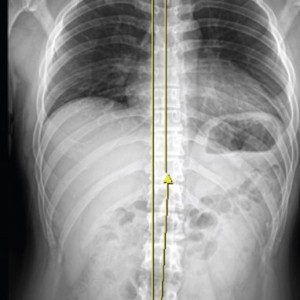

척추

척추측만증 또는 좌, 우 한쪽으로 기울어진 척추로 인해 체중이 한쪽 허리로 집중된다면 장기적으로 체중이 기울어진 쪽 허리에 뼈가 자라거나 퇴행성 변화가 빠르게 진행됩니다.